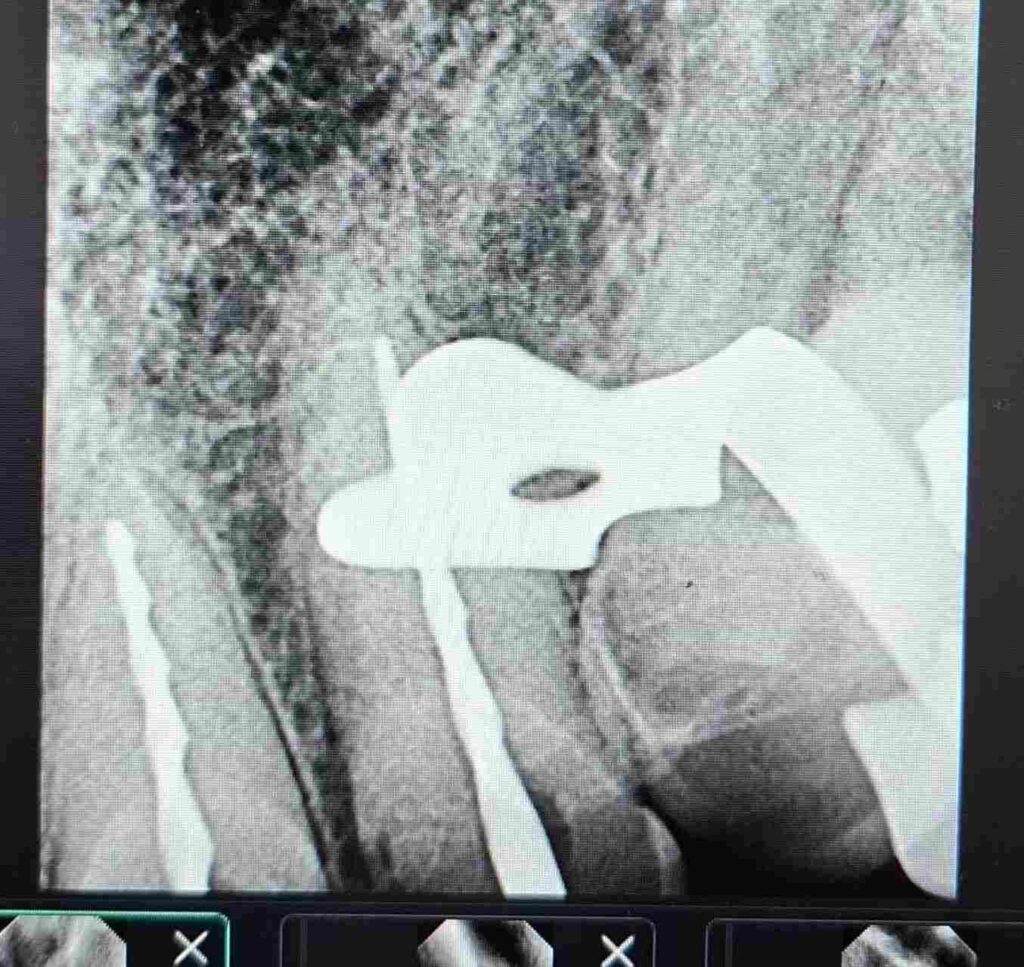

Durante todo el protocolo se realizaron irrigaciones activas con soluciones desinfectantes, garantizando la eliminación completa de detritos y microorganismos. Finalmente, se completó la obturación tridimensional del sistema radicular, logrando un sellado hermético confirmado por control radiográfico.

Este abordaje restauró la salud periapical y la estabilidad biológica de las piezas tratadas, constituyendo el primer paso clave dentro del plan de rehabilitación integral del paciente.